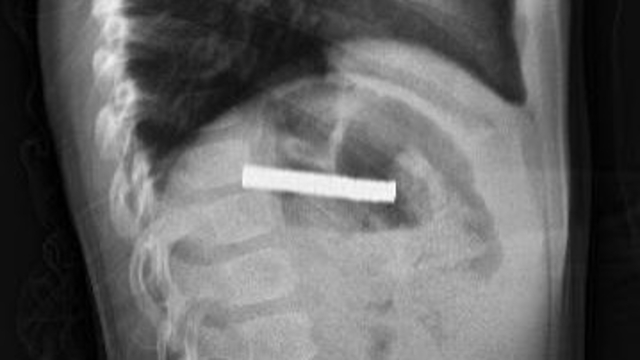

ERZURUM’da 3 yaşındaki bir çocuğun yuttuğu 19 mıknatıs, Elazığ’daki Fırat Üniversitesi Hastanesi’nde yapılan başarılı bir operasyonla çıkarıldı.

Erzurum’da 3 yaşındaki çocuk, evde oynadığı sırada 19 mıknatıs yuttu. Bir süre sonra rahatsızlanan çocuğun durumunu fark eden ailesi, hastaneye başvurdu. Yapılan ilk müdahalenin ardından çocuk, ileri tetkik ve tedavisi için Elazığ’daki Fırat Üniversitesi Hastanesi’ne sevk edildi. Fırat Üniversitesi Tıp Fakültesi Çocuk Gastroenteroloji, Hepatoloji ve Beslenme Bilim Dalı Başkanı Prof. Dr. Yaşar Doğan ve ekibi tarafından gerçekleştirilen operasyonla, çocuğun yemek borusuna yapışan 19 mıknatıs endoskopik yöntemle çıkarıldı. Mıknatısların, mide girişinde ve yemek borusunda zedelenmelere yol açtığı belirtildi. Çocuk tedavisinin ardından taburcu edildi.